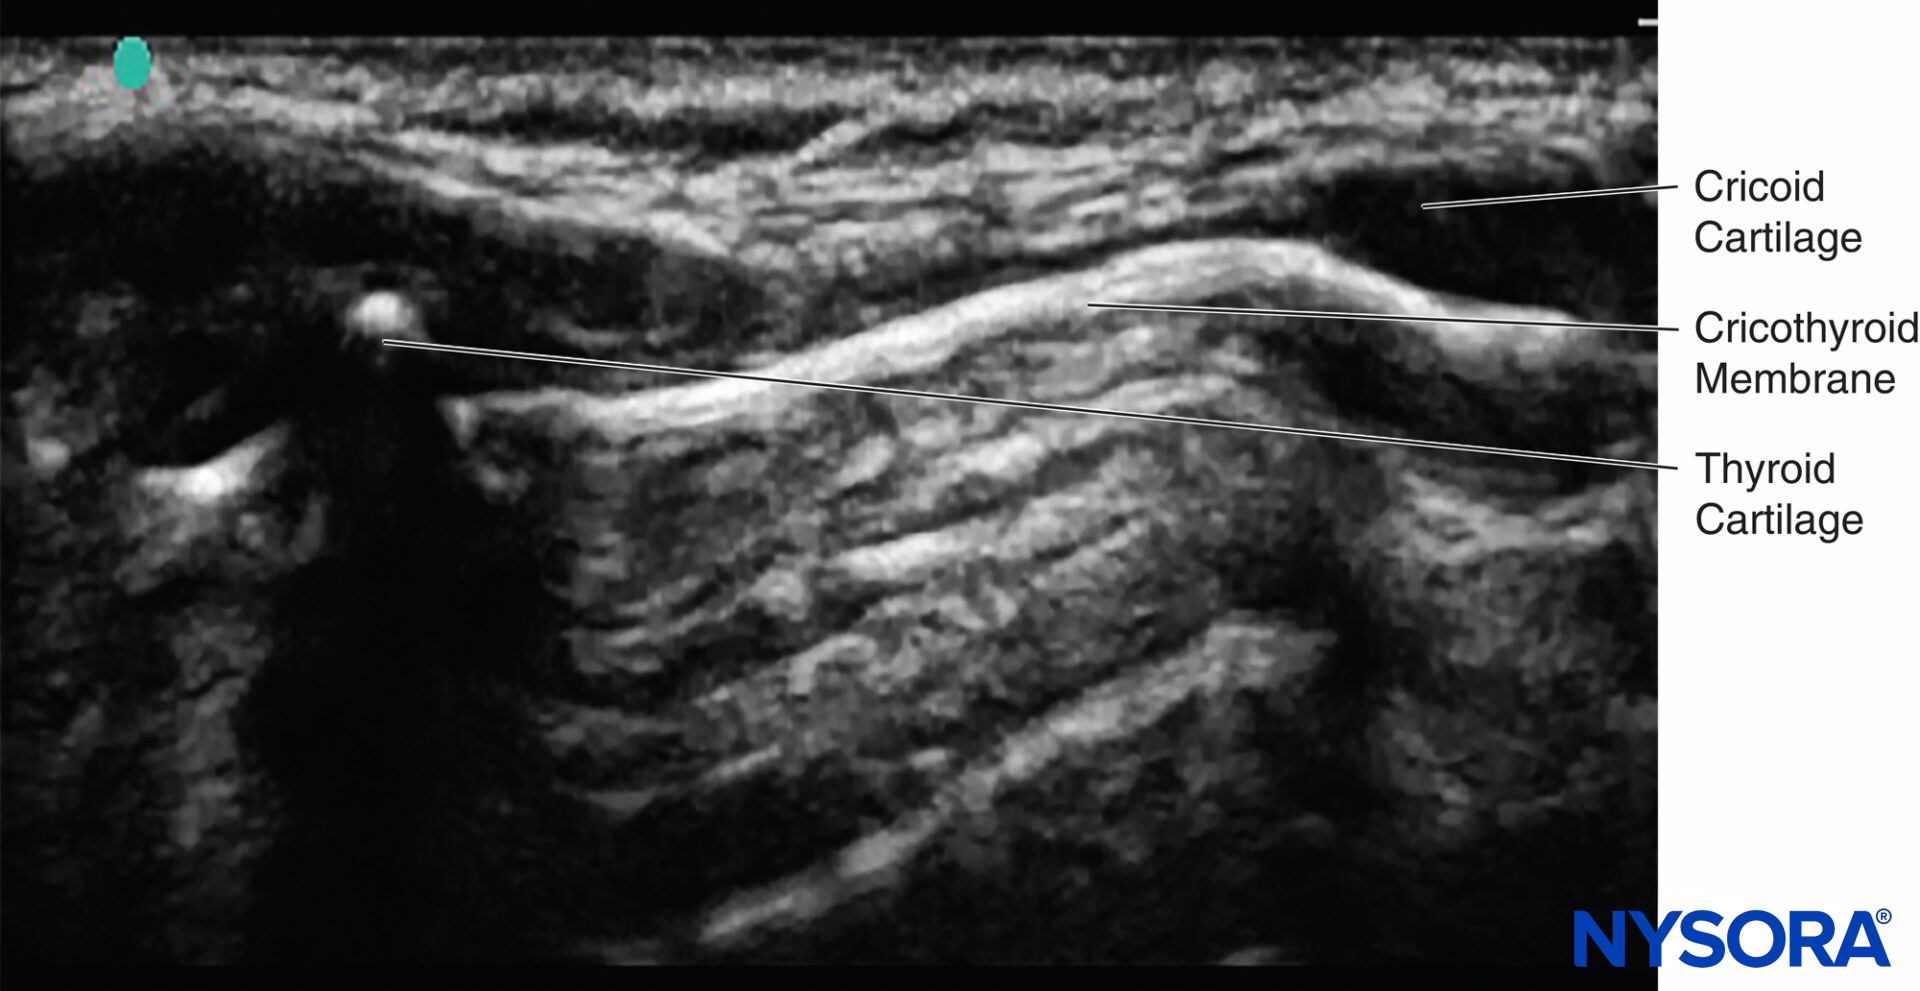

Translaryngeal Block

Sometimes, the correct location of the cricothyroid membrane is difficult to identify by palpation only. Ultrasound can be used to identify the thyroid and cricoid cartilages and the cricothyroid membrane (Table 3), ensuring that the local anesthetic is deposited correctly and a successful translaryngeal block is achieved19 (Figure 15).

FIGURE 15. Ultrasound image of cricoid cartilage, thyroid cartilage, saggital plane, and cricothyroid membrane.

If the probe is placed longitudinally in the midline of the neck, the tracheal rings can be seen. If the probe is then advanced cranially, the cricoid cartilage can be seen next; this is a slightly elongated structure that is larger and more superficial than the tracheal rings. If the probe is further advanced cranially, the thyroid cartilage can be seen. The cricothyroid membrane lies between the caudal border of the thyroid cartilage and the cephalad border of the cricoid cartilage. Keep the probe in the midline with the cricothyroid membrane in the middle of the image seen on the monitor; then, the exact location on the patient’s neck can be marked using a marker pen. Now that the position of the cricothyroid membrane has been located, the translaryngeal block can be performed.

The block can also be performed under real-time sonography by simply tilting the probe from the midline to a parasagittal position, keeping the cricoid cartilage in view. The needle entry point should be just cranial to the cricoid cartilage and can be seen on the ultrasound monitor (Figure 16). Once air is aspirated, this confirms that the needle is through the membrane and in the trachea.